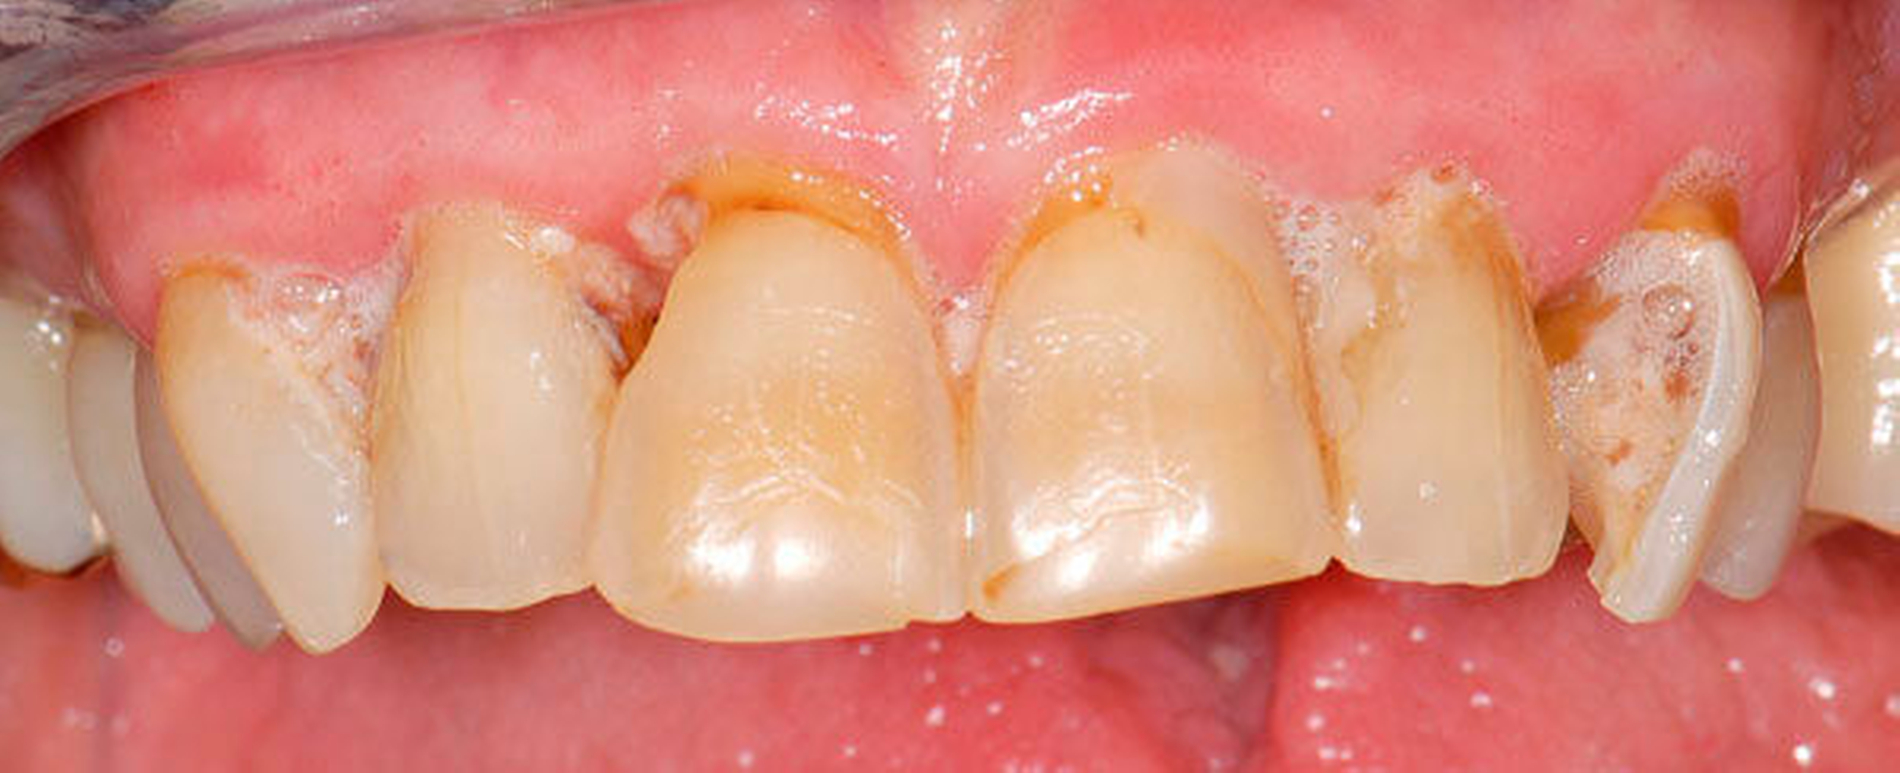

Abbildung 1 A-I: 84-jähriger Patient mit arterieller Verschlusskrankheit (Claudicatio intermittens)

Senioren haben – wie oben ausgeführt – immer häufiger zahlreiche eigene Zähne. Im Fall von Lückenbildungen müssen diverse Behandlungsalternativen in Erwägung gezogen werden. Dazu zählen neben klassischen prothetischen und implantologischen Versorgungen auch andere Optionen (Tabelle 1). Nicht jede Lücke muss geschlossen werden. Wenn funktionell und ästhetisch keine relevanten Einschränkungen bestehen, kann auch ein Monitoring (Belassen und Beobachten) eine gute Lösung sein [Staehle, 2010; Listl et al., 2016]. Daneben kommen zuweilen Zahnumformungen und -verbreiterungen (Abbildung 1) oder direkte Freiendanhänger aus Komposit als Behandlungsmittel zum Lückenschluss in Betracht [Staehle, 2007, 2009, 2010, 2012, 2017; Staehle et al., 2014, 2015a, b; Frese und Staehle, 2018]. Schließlich ist für Patienten, bei denen aufwendiger festsitzender Zahnersatz nicht möglich ist und die keine herausnehmbare prothetische Versorgung wünschen, die Verfolgung des Prinzips der verkürzten Zahnreihe [Walter, 2016] zuweilen eine gute Alternative. Zur praktischen Realisierung dieses Konzepts kann heute die konservierend-restaurative Zahnheilkunde (zum Beispiel über Zahnverbreiterungen und -anhänger, eventuell in Kombination mit Schienungen) ebenfalls viel beitragen.